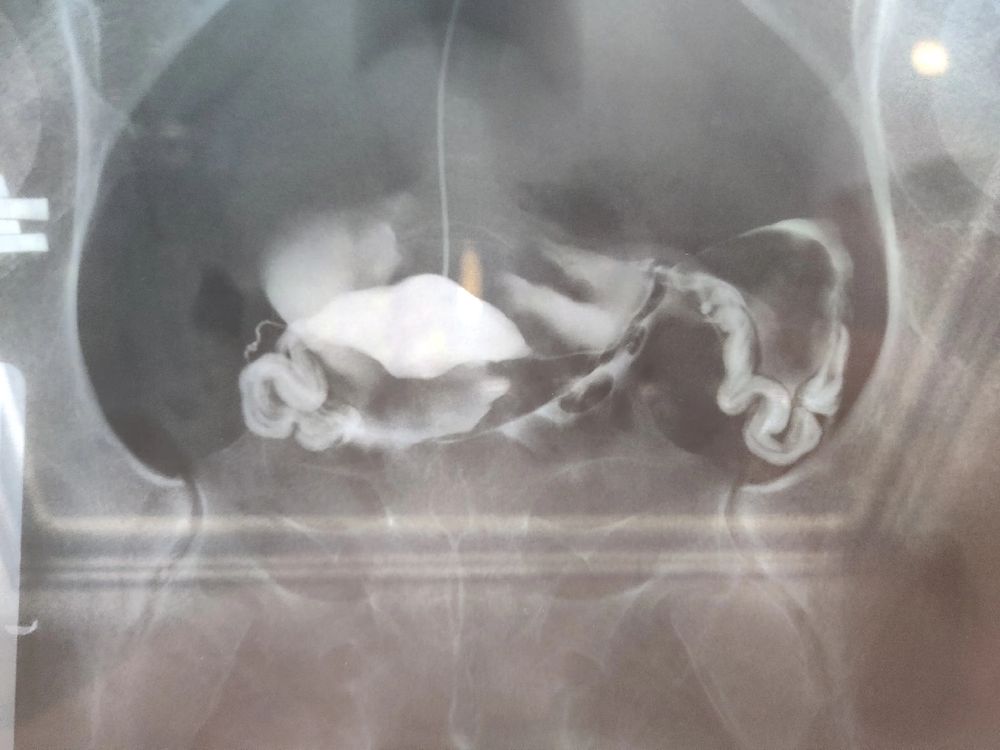

3. На гсг (проверке проходимости маточных труб) врач удивился, как такие трубы могут быть в 25 лет. Трубы сильно извитые , без пристальтики (тонуса) в них, то есть нефункциональны. Но оказались проходимы при введении в них йода. Так же были обнаружены спайки. Выяснили, что трубы стали такими вследствие перенесенного когда-то хламидиоза, о котором я даже не подозревала. В мазке ничего не определяется , об этом узнали по ИФА анализу крови.

Прикрепила рентген снимки труб и заключение по ним.